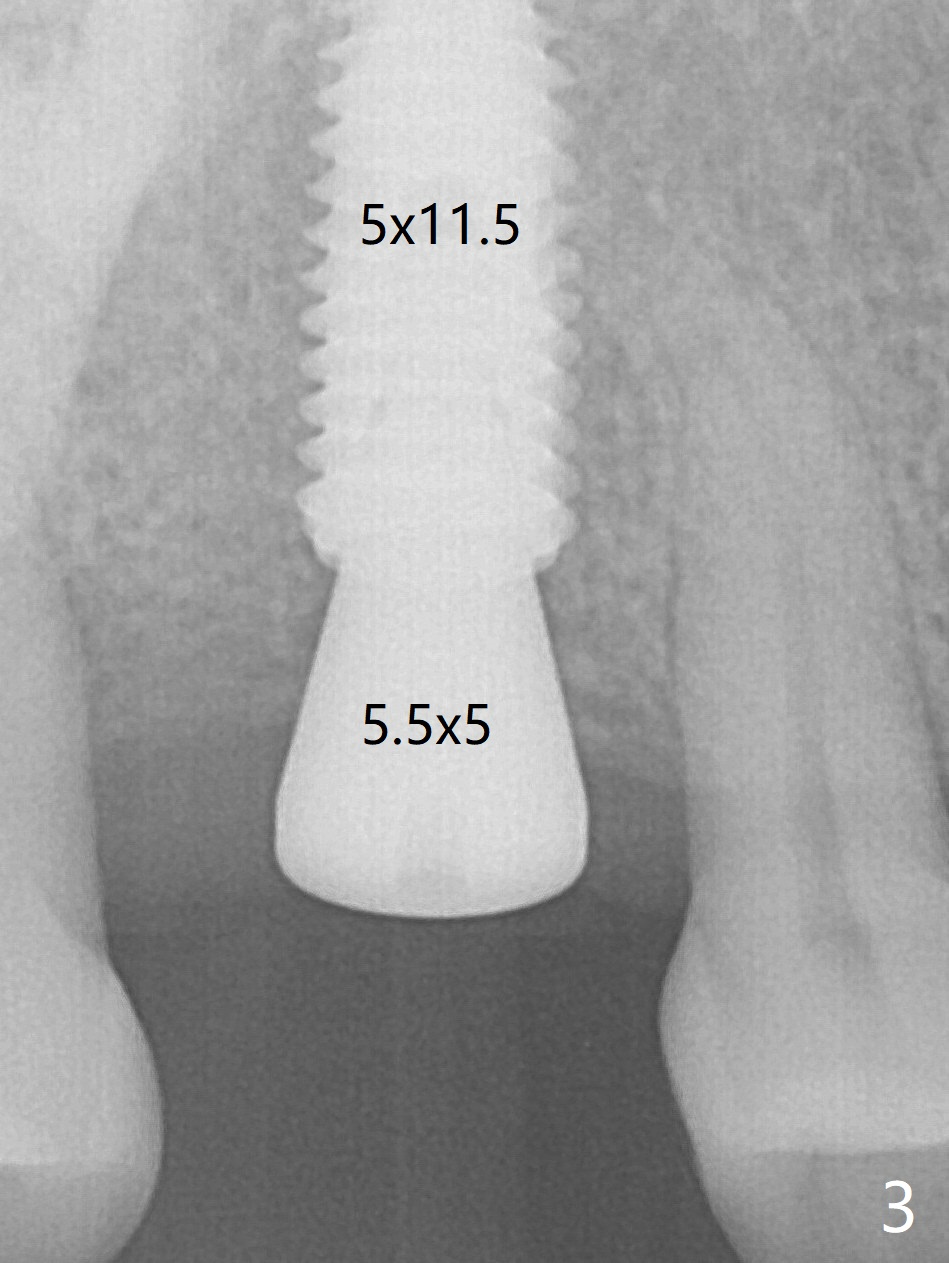

After finishing osteotomy according to the guide plan, a 3.5x13 mm drill is used ~ .5 mm shy of the depth without sign of sinus membrane leakage. The implant is placed with apparently satisfactory depth, but it is quite close to the curved root tip of the neighboring tooth (Fig.2,3). The implant is stable for impression 6.5 months postop (Fig.5), whereas that placed immediately free hand is unstable 7.5 months postop.